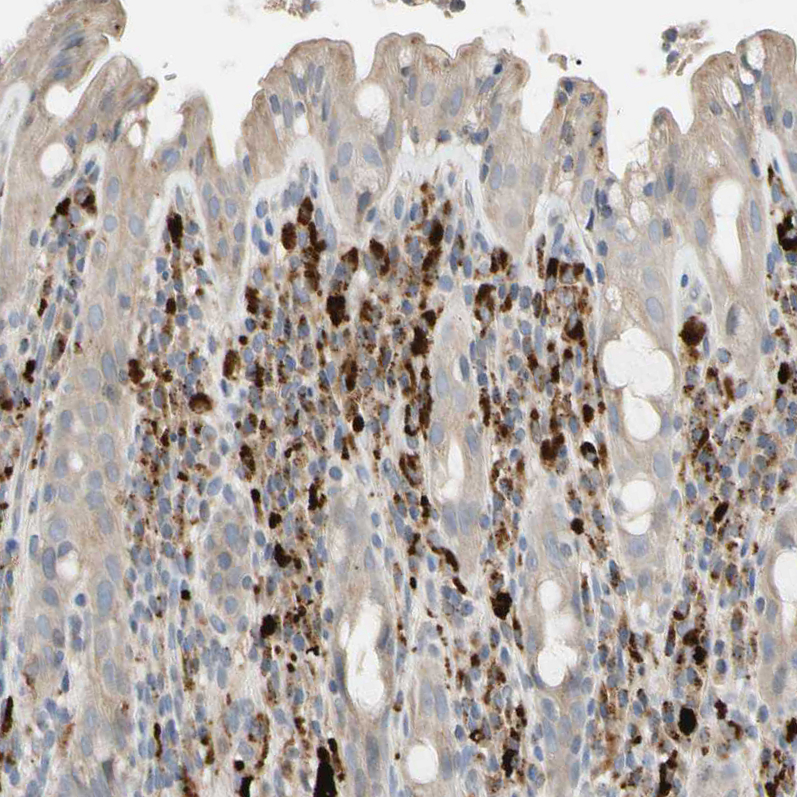

Immunohistochemical staining of human rectum shows strong cytoplasmic positivity in lymphoid cells.